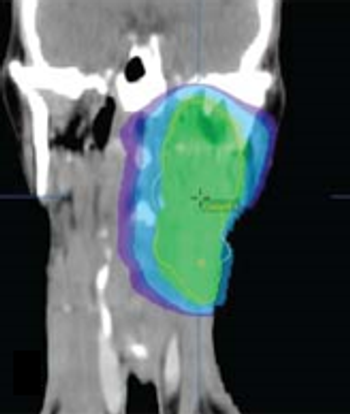

Tumor shrinkage is a valid indicator of response to VEGF inhibition among patients with metastatic renal cell carcinoma when evaluated by a single radiologist observer.